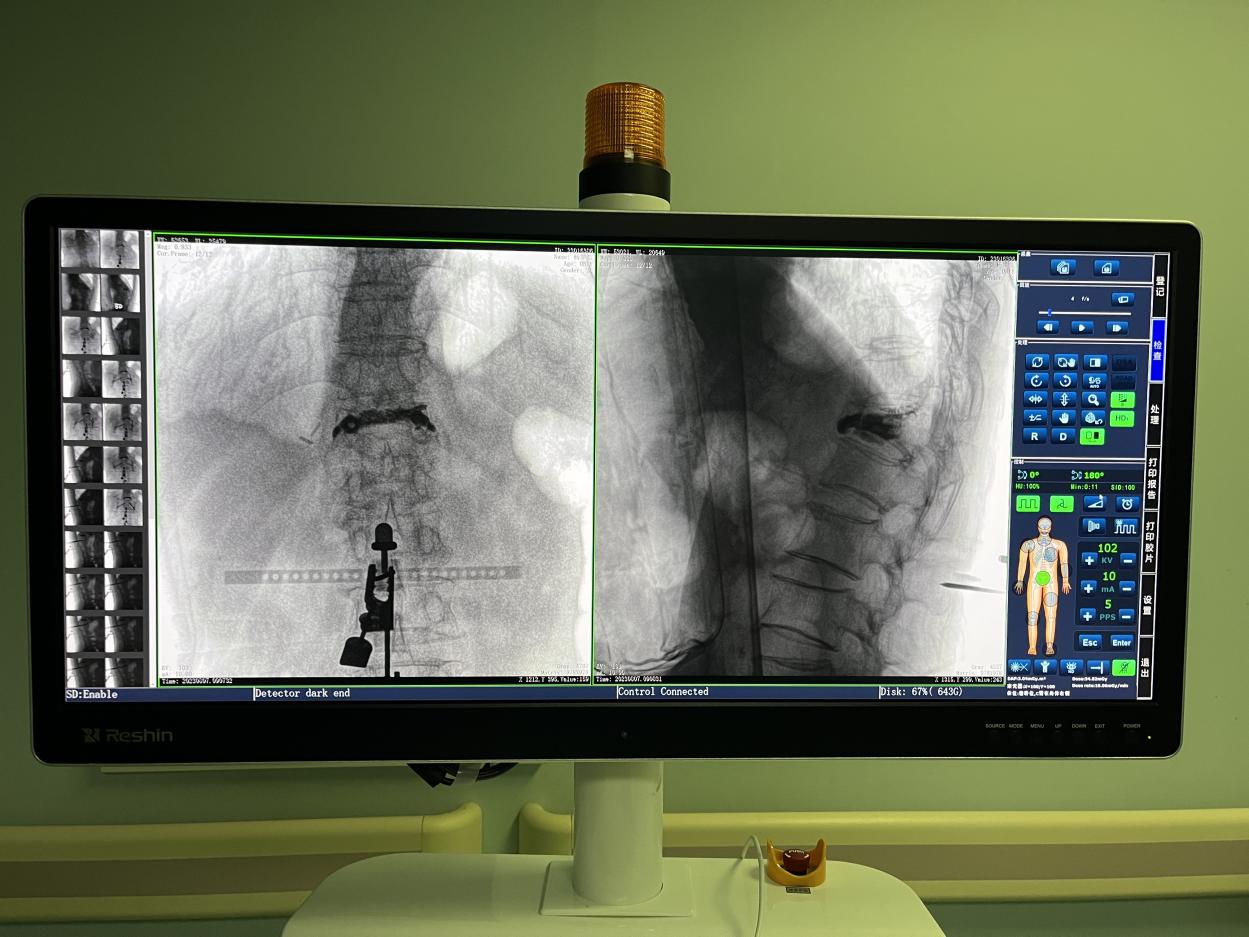

骨科機器人手術-術后影像

目前,普愛醫療骨科手術機器人已在江蘇省人民醫院、南京醫科大學第二附屬醫院等多家醫院投入使用,臨床反饋良好,幫助醫患降低手術風險的效果顯著。